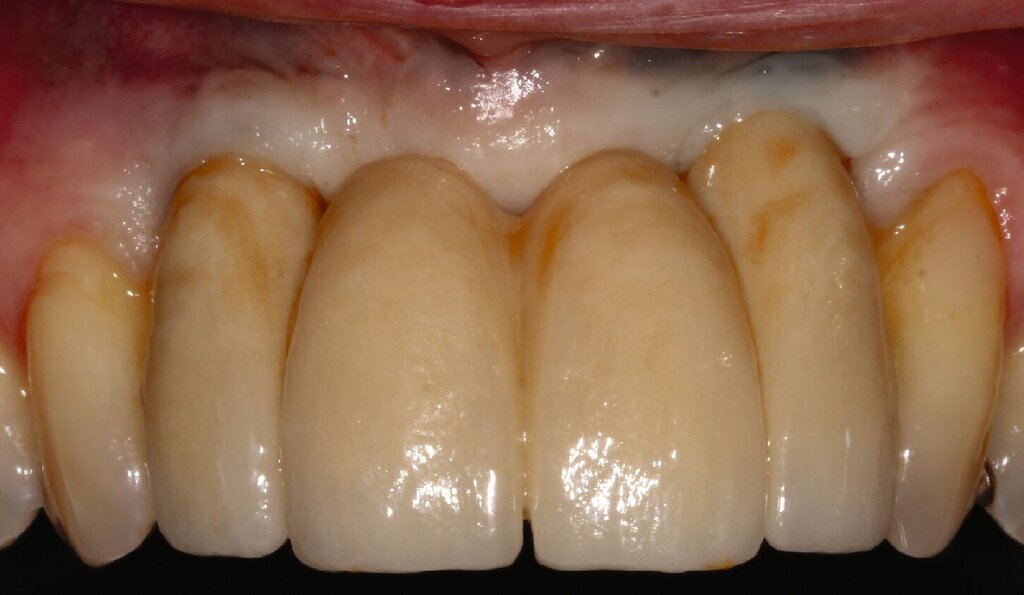

Bei einem 76-jährigen Patienten wurde ein circa 20 Jahre altes Aluminiumoxid-Implantat (Abb. 2a) entfernt, nachdem die ausgeprägte Gingivarezession in Kombination mit dem Abbau der vestibulären Knochenlamelle keine ausreichende Mundhygiene mehr zuließ. Nach Entfernung der Krone auf dem intakten Implantat in regio 11 konnte zur provisorischen Lückenversorgung eine stuhlgefertigte, kombiniert Zahn/Implantat-gestützte Brücke von 011 auf 22 eingegliedert werden (Abb. 2b). Eine Nachimplantation war aufgrund der günstigen Prognose für den Pfeilerzahn 22 überflüssig. Das verbliebene Weichgewebsdefizit wurde drei Monate nach der Explantation mit einem Bindegewebstransplantat vom harten Gaumen kompensiert (Abb. 2c bis 2e). Nach einer Konsolidierungsphase von weiteren drei Monaten wurde das Provisorium durch eine monolithische Zirkoniumdioxidbrücke mit ausschließlich vestibulärer Verblendung ersetzt (Abb. 2g). Eine invasive knöcherne Augmentation mit Wiederherstellung des knöchernen Kieferkamms nach dem Implantatverlust in regio 21 konnte vermieden werden, da eine erneute Implantation für das Behandlungsziel einer festsitzenden Versorgung nicht nötig war.